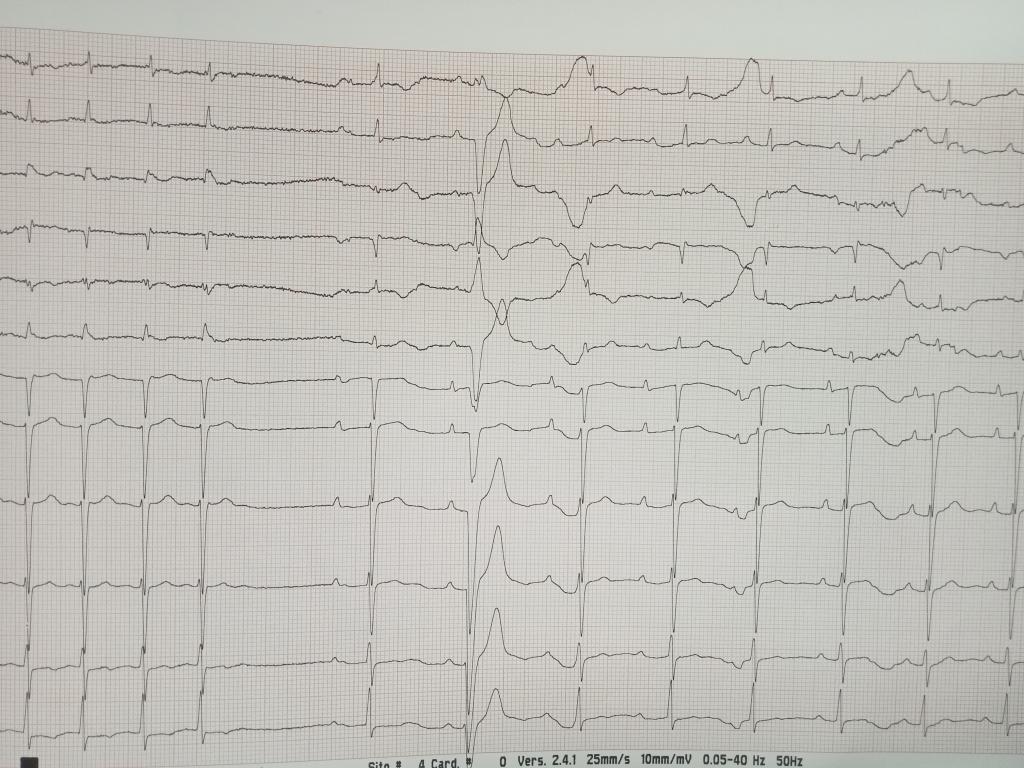

@IrmaMDv Not much doubt about automatic NSVT (instead of escape mechanism due to sinus dysfunction). I'd say the escape QRS after the termination of VT was from lower junction. Obviously I think we know what 'automatic VT' means.

@IrmaMDv Escape beat at a low rate usually has broader QRS. One can see it also after adenosine for AVNRT that during the AV block from adenosine there are one or two broader beats.

@IrmaMDv What about the strip with two ectopies shown later in the rhythm strip. There seem no big pauses after them. Sinus is overall around 60 bpm. Probably no sinus node dysfunction. Were there slower sinus rates or long pauses after isolated PACs (or SVTs when present)?

@IrmaMDv Tiny P waves (difficult to see AV dissociation or retroconduction). Perhaps one P can be seen at the end of ST of the 1st QRS in this short run of VT at the rate of cca 120 bpm (not 85 as written) with sinus cca 60 bpm. The last broad beat is bradycardia dependent bundle block.

@IrmaMDv AF with SVR and intermittent complete AVB with VER.

V pacing and sensing failure.

NSVT 4beats.